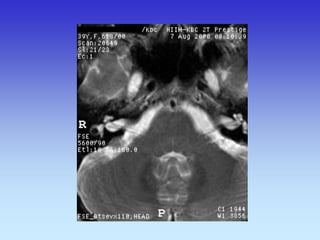

Rhombencephalon (Hindbrain) Inferior Cerebellar Peduncle

Temporal Lobe

Pons

Fourth Ventricle

Maxillary Sinus Middle Cerebellar Peduncle